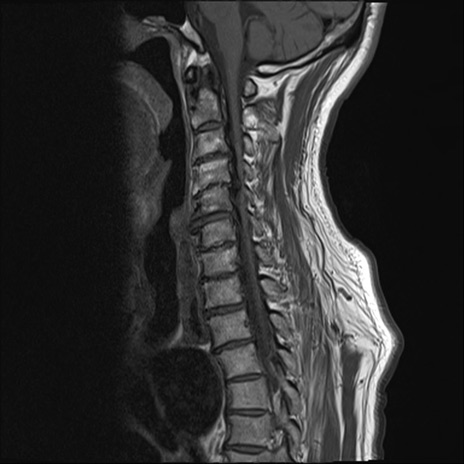

【整形】TIPS症例7 頚椎MRI T1WI(矢状断像)

頚椎MRI

T2WI(矢状断像)